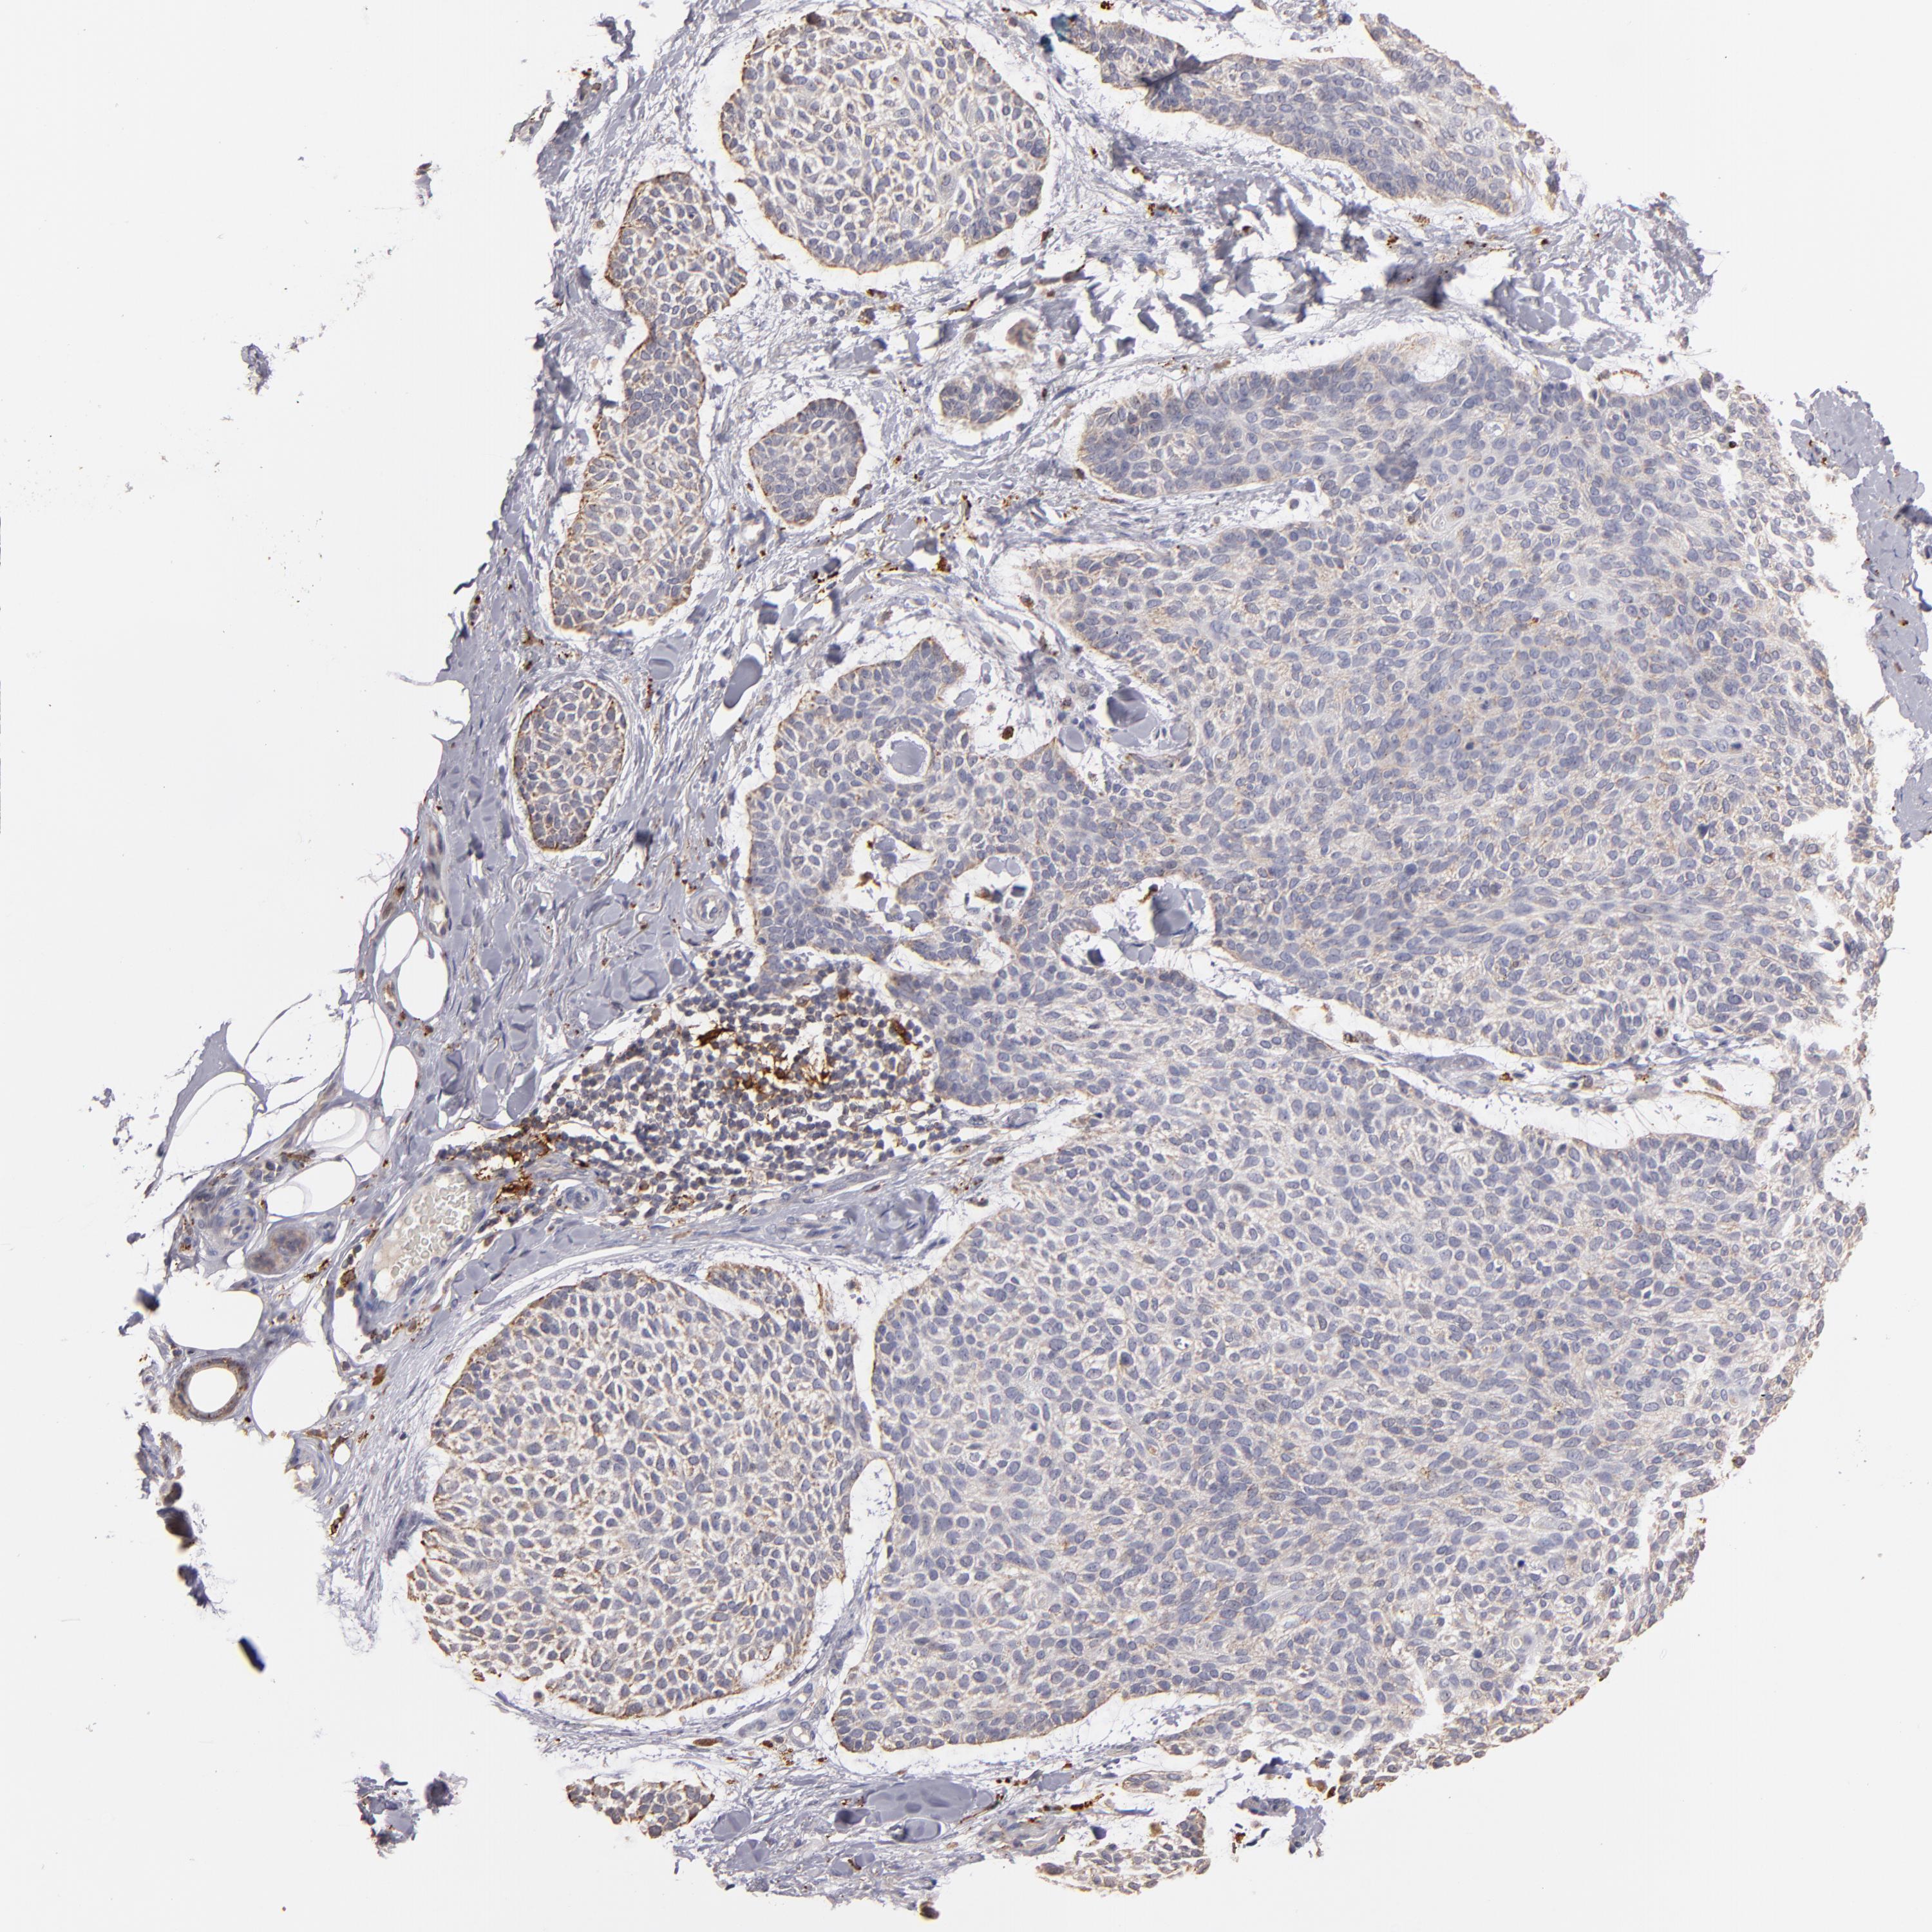

SKIN CANCER - Protein expressioni

A mouse-over function shows sample information and annotation data. Click on an image to view it in a full screen mode. Samples can be filtered based on level of antibody staining by selecting one or several of the following categories: high, medium, low and not detected. The assay and annotation is described here.

Each image is clickable and will lead to virtual microscopy that enables deeper exploration of all samples and also displays staining intensity scores, fraction scores and subcellular localization as well as patient and tissue information for each sample.

Antibody HPA001852

Squamous cell carcinoma, NOS

Basal cell carcinoma